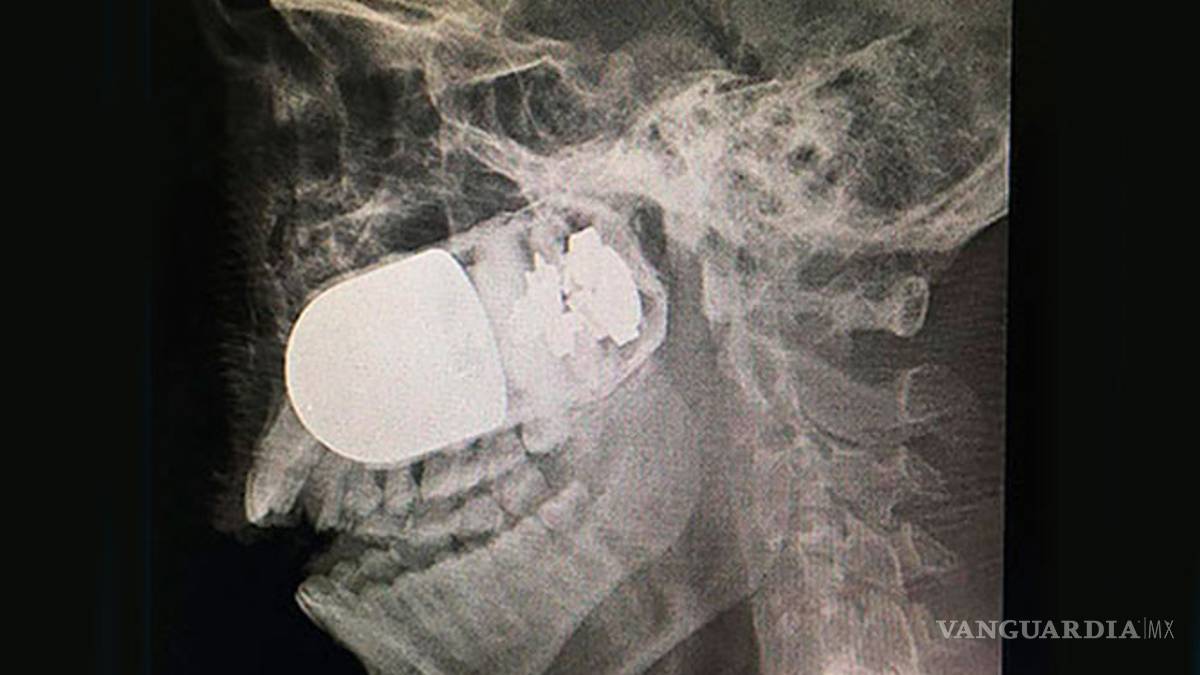

La cirugía para extraer una granada de asalto incrustada en el rostro de un soldado colombiano es un hecho excepcional y único en el mundo, porque estuvo en riesgo la vida del paciente y de todo el equipo médico del Hospital Militar Central, en esta capital.

El médico jefe de cirugías del Hospital Militar Central, William Sánchez, explicó a la prensa local que el soldado Leandro José Luna llegó el domingo pasado al centro hospitalario procedente del departamento de Arauca, en el suroccidente del país, por vía terrestre, ante la imposibilidad de trasladarlo en avión.

Explicó que el soldado no podía ser trasladado vía aérea por el riesgo que explotara la granada de asalto M40, que tenía incrustada en el rostro. Por esta razón fue movilizado en una ambulancia durante un recorrido de más de ocho horas.

El pasado fin de semana, el soldado estaba patrullando en las inmediaciones del río Tame, Arauca, cuando uno de sus compañeros activó en forma accidental un lanzagranadas MGL, y como consecuencia una granada se le incrustó en el rostro de Luna.

El militar “llegó en estado crítico al hospital y se tomó la decisión de atender con rapidez al paciente. El equipo quirúrgico tenía un riesgo muy elevado”, señaló Sánchez.

Insistió que este es un caso inusual, único a nivel mundial, porque se tuvo que montar todo el dispositivo médico para la cirugía en el estacionamiento a cielo abierto del Hospital Militar Central, con apoyo de expertos en explosivos para tener controlada la granada.

Fue una intervención de altísimo riesgo para el paciente y el equipo médico por el alto poder explosivo que tienen las granadas de asalto, que son utilizadas en la confrontación armada que vive este país desde hace 52 años de guerra.

Después de la exitosa intervención, el soldado se encuentra estable y en recuperación.